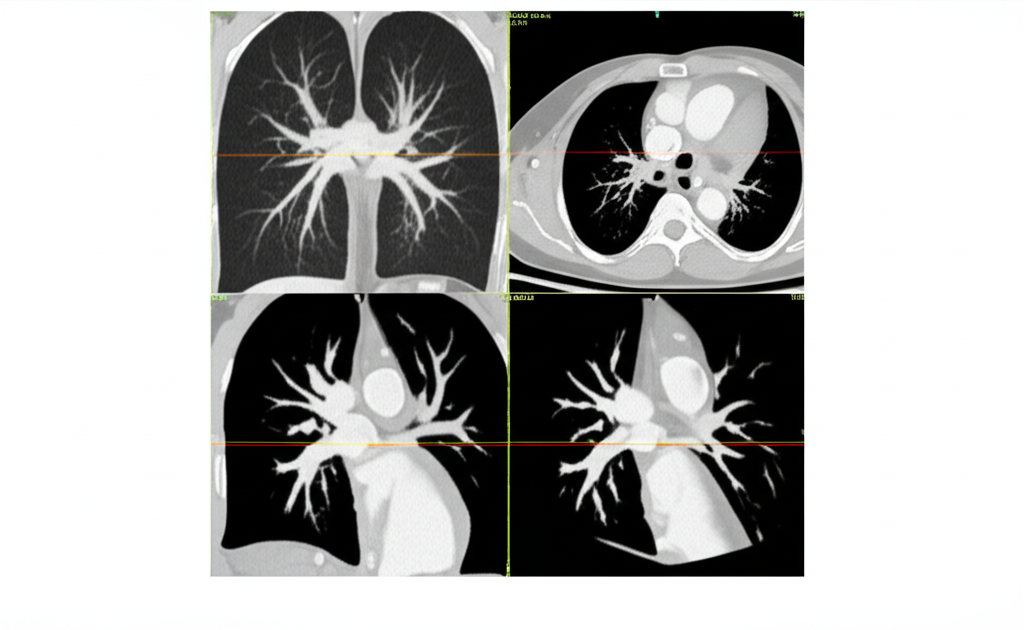

심장 CT(Computed Tomography)는 컴퓨터 단층 촬영 기술을 이용하여 심장의 단면 영상을 얻는 검사입니다. 기존의 엑스레이 촬영보다 훨씬 더 자세하고 정확한 이미지를 제공하여, 심장 질환의 조기 진단과 치료 계획 수립에 큰 도움을 줍니다. 심장 CT는 특히 관상동맥 질환, 심장 판막 질환, 심근 질환 등 다양한 심장 질환을 진단하는 데 유용합니다.

- 관상동맥 질환 진단: 관상동맥 CT는 관상동맥의 협착이나 폐쇄 여부를 정확하게 진단할 수 있습니다. 특히, 칼슘 스코어링을 통해 동맥경화의 정도를 평가하고, 향후 심혈관 질환 발생 위험을 예측할 수 있습니다.

- 심장 구조 평가: 심장의 크기, 모양, 위치 등을 정확하게 파악하여 심장 비대, 심방중격결손, 심실중격결손 등 선천성 심장 질환이나 심장 구조 이상을 진단할 수 있습니다.

- 심장 기능 평가: 심장의 수축력과 이완력을 평가하여 심부전 진단에 도움을 줄 수 있습니다. 심장 CT는 심장의 각 부위별 기능을 평가하여, 심부전의 원인을 파악하는 데 중요한 정보를 제공합니다.

- 대동맥 질환 진단: 대동맥류, 대동맥 박리 등 대동맥 질환을 진단하고, 대동맥의 크기와 모양을 평가할 수 있습니다.